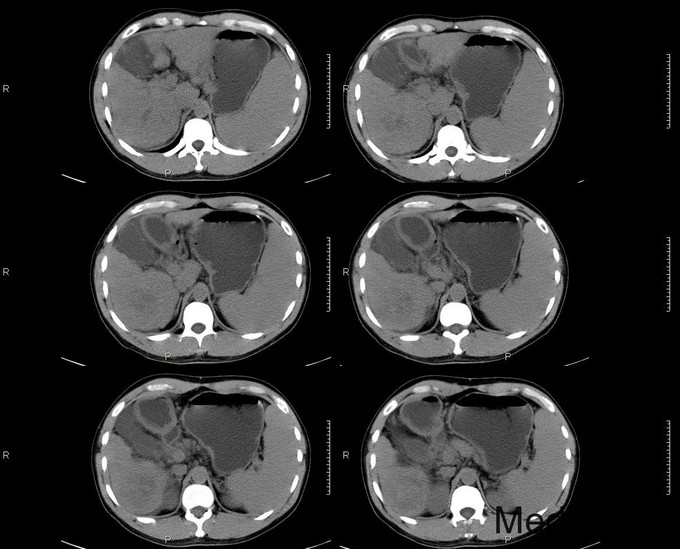

主诉:反复乏力、纳差2月余。身目黄染1月余。 病史:患者中老年男性,2月前出现乏力、纳差,查乙肝两对半示大三阳,上腹部CT示肝硬化,予护肝等治疗后好转出院。1月前天前出现身目黄染,伴瘙痒,再次入院。 既往史:患者有肝癌家族史(父亲肝癌去世)

查体:慢性肝病体征,肝掌阳性,蜘蛛痣阳性,胸前毛细血管扩张,腹水征阳性,肝脾肋下可触及。 辅查:生化:谷草146,谷丙110,总胆184,直胆114,白蛋白38,凝血四项:PT17.9s,PTA56。 CA-125: 600,CA-199:54.13,AFP:98.73。 肝彩:1、肝硬化,肝左叶可见高回声团。 上腹部CT: 肝癌、肝硬化、脾大

诊断:1、原发性肝癌;2、乙肝肝硬化 1、常规护肝退黄降酶,输血浆,护胃制酸等对症支持治疗 2、转肝脏外科。